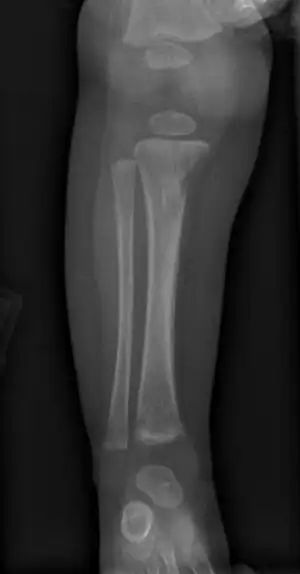

Refusal to move a limb in an infant may result from inflammation around bone or cartilage.[1]

Late onset features include deformity of the nose, lower legs, forehead, collar bone, jaw, and cheek bone.[1] Some of these bone defects can be detected early.[16] There may be a perforated or high arched palate, and recurrent joint disease.[1][4] Other late signs include scarred skin, intellectual disability, hydrocephalus, and juvenile general paresis.[1] Eighth nerve palsy, interstitial keratitis and small notched teeth may appear individually or together; known as Hutchinson triad.[1][18]